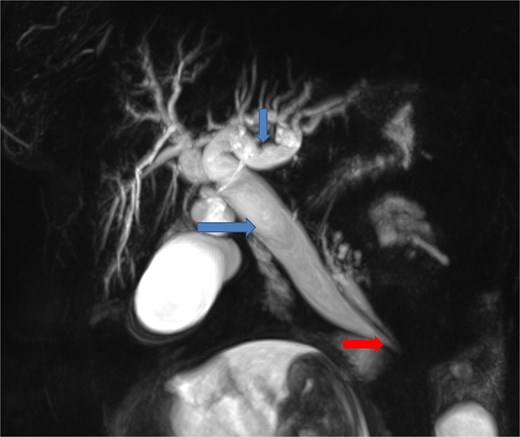

To better assess the biliary anatomy and clarify the cause of obstruction, a MR cholangiopancreatography (MRCP) was performed 2 days later. It confirmed the duodenojejunal invagination and demonstrated the involvement of the terminal bile duct within the intussuscepted segment (Fig. 4). An ectopic biliopancreatic confluence was also identified, draining into the fourth portion of the duodenum, likely predisposing the bile duct to traction and resulting in upstream dilation (Fig. 5).

Coronal MR cholangiopancreatographic image showing an ectopic biliopancreatic confluence draining into the fourth portion of the duodenum (arrow at the bottom), which likely predisposed the biliary system to traction during the intussusception, resulting in upstream biliary duct dilatation (two arrows at the top).